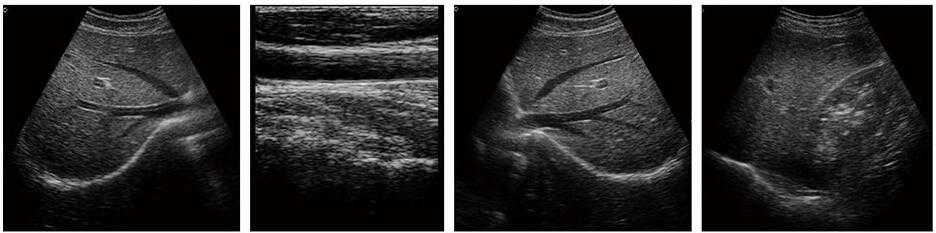

多倍率顯示,病變?cè)\斷更精確

角度視野調(diào)節(jié)更靈活